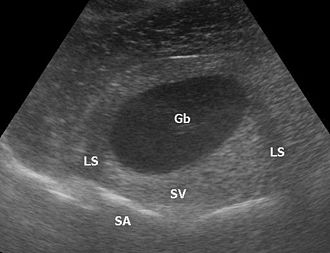

Die Sonografie ist das wichtigste Verfahren bei der Differentialdiagnose eines akuten Abdomens, bei Gallensteinen oder bei der Beurteilung von Gefäßen und deren Durchlässigkeit, vor allem an den Beinen. Weiterhin wird sie standardmäßig zur Untersuchung der Schilddrüse, des Herzens – dann Echokardiografie oder Ultraschallkardiografie (UKG) genannt –, der Nieren, der Harnwege und der Harnblase benutzt. Durch den Einsatz von Echokontrastverstärkern (Kontrastmittel) ist in geeigneten Fällen eine weitere Verbesserung der Diagnostik möglich.

Ein häufiges Artefakt ist die Abschattung (distale Schallauslöschung) hinter stark reflektierenden Objekten mit einer vom übrigen Gewebe stark abweichenden Impedanz wie Knochen, Luft oder Konkrementen (Ablagerungen). Bei nahezu senkrechtem Schalleinfall gibt es ein starkes Echo, bei schrägem Einfall nicht.

Eine distale Schallverstärkung ist ein übermäßig hell dargestelltes Gewebe hinter (distal) einer Struktur, die wenig dämpft. Allgemein wird, um die Dämpfung des Gewebes auszugleichen und zum Beispiel Lebergewebe über die gesamte Tiefe homogen darzustellen, mit Hilfe der time gain compensation oder auch depth gain compensation, tiefer liegende Signale zunehmend verstärkt. Zum Beispiel bei einer Gallenblase in der Leber ist das Lebergewebe deutlich heller als das restliche Lebergewebe, weil Galle weniger dämpft als Lebergewebe, aber das Gewebe hinter der Gallenblase mit dem gleichen Verstärkungsfaktor aufgehellt wird wie das umliegende Gewebe.